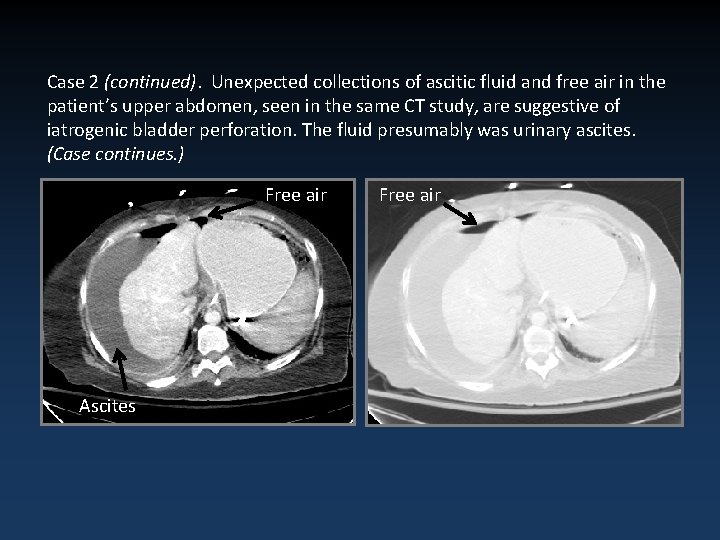

Case 2 (continued). Unexpected collections of ascitic fluid and free air in the patient’s upper abdomen, seen in the same CT study, are suggestive of iatrogenic bladder perforation. The fluid presumably was urinary ascites. (Case continues. ) Free air Ascites Free air